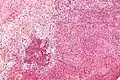

- Micrograph of a schwannoma showing both a cellular Antoni A area (top) and a loose paucicellular Antoni B area (bottom). HE stain.